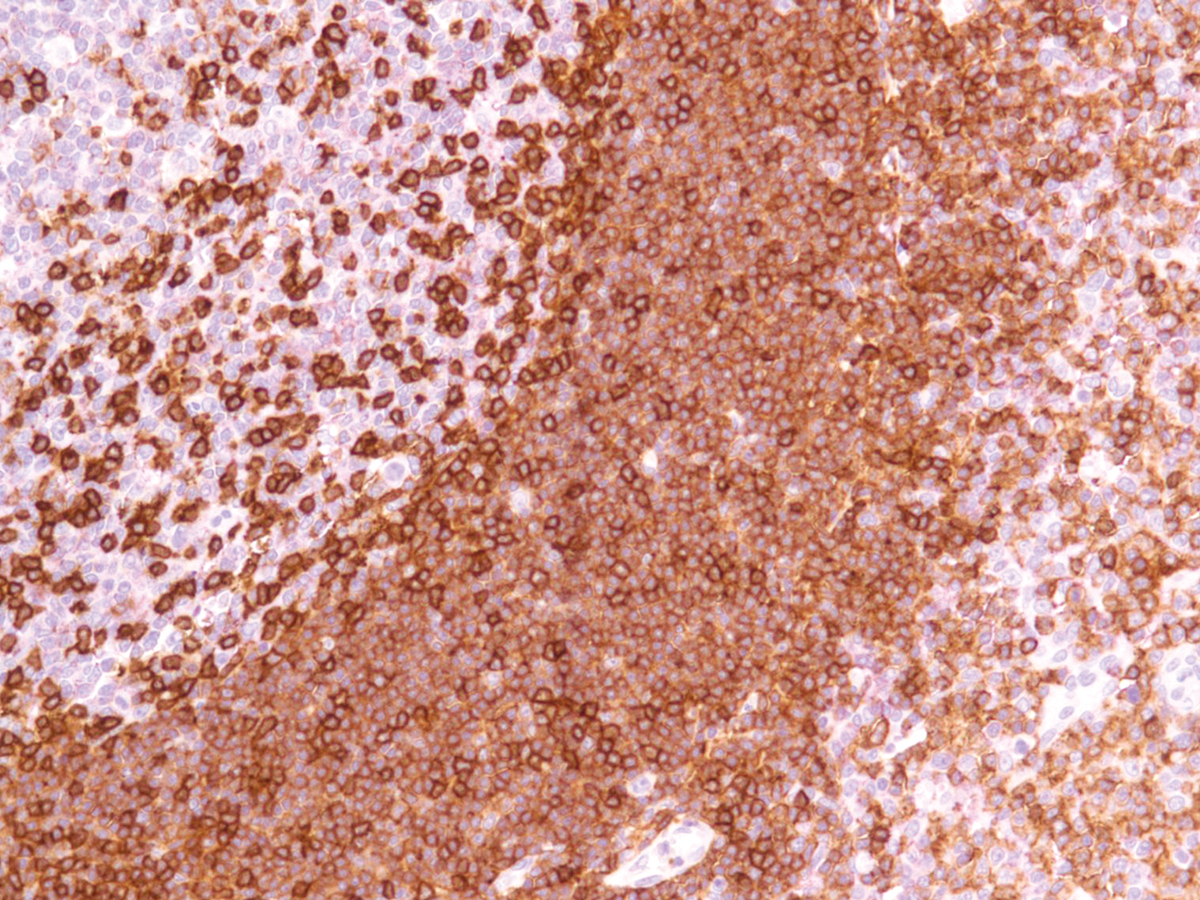

Anti-FSH Monoclonal Antibody (Clone:IHC580)

Figure 1: Immunohistochemical analysis of FSH (IHC580) on Pituitary Gland

Follicle-Stimulating Hormone (FSH) allows for progression of ovarian folliculogenesis, and enables Sertoli cell proliferation in the testis. Anti-FSH reacts with FSH-producing cells, therefore FSH staining is useful for classifying pituitary cancers and understanding pituitary disease.

Recommended dilutions: Immunohistochemical analysis: 1:100 - 1:200. However, this need to be optimized based on the research applications.